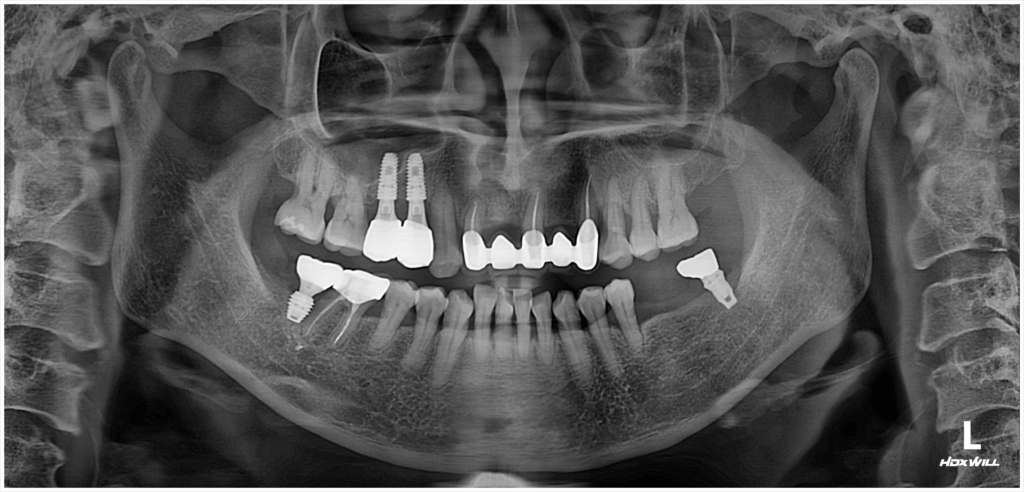

술전 사진

2025.01.13

이번에 내원하신 환자분은 왼쪽 아래 치아 부위의 문제로 방문해 주셨습니다. 첫 내원 시 촬영한 방사선 검사에서 이미 잇몸뼈의 일부가 흡수된 상태임을 확인할 수 있었으며, 해당 부위는 염증과 함께 치아 흔들림이 동반되어 있었습니다. 환자분께서 통증과 저작하는 부분에서 불편을 지속적으로 호소하셨기 때문에 발치를 피하기는 어려운 상황이었습니다.

특히, 문제된 치아 바로 옆에는 이미 과거에 발치된 빈 공간이 있었고, 치료 계획대로 진행할 경우 양쪽 치아 부위를 모두 임플란트로 보강해 하나의 브릿지 형태로 복원해야 했습니다. 만약 일반적인 순서로 발치 후 치조골 회복을 기다린다면, 전체 치료 기간이 길어질 수밖에 없는 구조였고, 그 사이 기능적인 불편도 지속될 우려가 있었습니다.

하지만 임상 경험이 풍부한 의료진의 판단 하에 해당 부위는 골 상태나 염증 범위를 고려했을 때, 발치 후 즉시 임플란트 식립이 가능하다는 결론을 내릴 수 있었습니다. 결과적으로, 환자분은 회복 기간을 줄이면서 동시에 양쪽 부위의 브릿지형 임플란트를 한 번에 진행할 수 있었고, 불필요한 내원 횟수나 치료 비용 부담 또한 줄일 수 있었습니다.